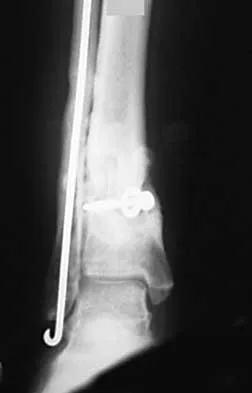

Question 22High Yield

A 68-year-old woman who sustained a closed distal tibia fracture 2 years ago was initially treated with an external fixator across the ankle for 12 weeks, followed by intramedullary nailing of the fibula and lag screw fixation of the tibia. She continued to report persistent pain so she was treated with a brace and a bone stimulator. She now reports pain in her ankle. Examination reveals ankle range of motion of 8 degrees of dorsiflexion to 25 degrees of plantar flexion. She is neurovascularly intact. Current radiographs are shown in Figures 9a through 9c. What is the next most appropriate step in management?

Explanation